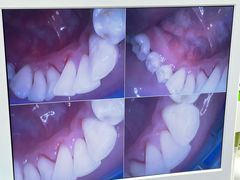

• 牙博士口腔品牌连锁(杨浦店)

• -牙博士口腔品牌连锁(杨浦店)

豆沙拉 | 23-04-23